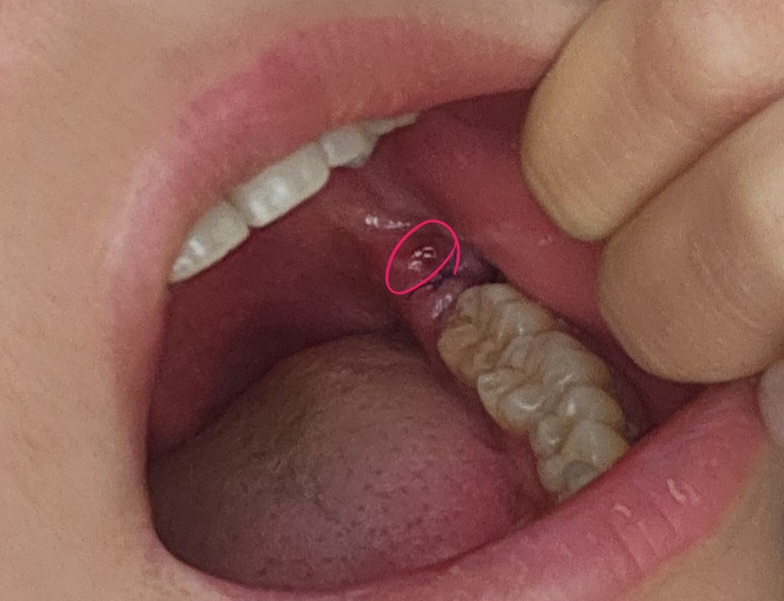

사랑니 발치 후 잘 아물고있는지 확인 부탁드립니다.

2월16일 금요일 오전 매복사랑니 발치했습니다.

3. 사진에 동그라미친 부분은 빨간데 왜그런건가요? 정상인가요?

• 1번 째 사진

일시적으로 해당부위에 자극감으로 인해 붉어질수 있습니다.